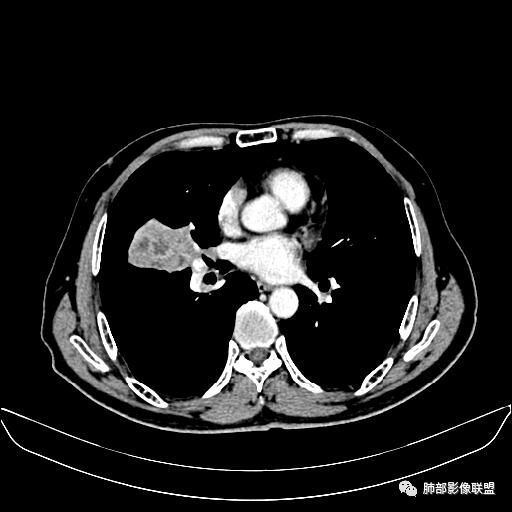

住院4天后行胸部增强CT

静脉期

右肺中叶软组织肿块,外围向内生长,叶间胸膜向前内移位,肿块近肺门侧跨叶,中叶外侧段支气管截断,密度不均匀,双侧肺门及隆突下见肿大淋巴结,增强后呈中度不均质强化,肺动脉供血,多发坏死区,边界尚清,坏死区域内见结构,结合病史考虑恶性,鉴别诊断1结核,爬行征是沿支气管树分布,外宽,内窄,周围有卫星灶,内气管狭窄后扩张,此例沿叶间胸膜长轴分布,气管有截断,不典型。2炎性肉芽肿,符合的地方下方层面增强后延迟性轻度环形强化,不符临床无发热等急性感染病史,实验室指标不符,病灶周围渗出及慢性炎性改变有,不明显。

吴婧老师和南边老师都对该病例进行了深入分析。从支气管管壁的增厚,支气管狭窄后扩张,支气管粘液栓,病灶形态,到病灶不均匀强化及坏死彻底,到周边病灶及肺组织空气的潴留,加之纵隔内淋巴结肿大伴钙化等等,都支持慢性炎性病灶,尤其是结核。

墨西哥仙人掌征---结核        影像上结核灶,粗大的均匀枝干,推测是支气管囊状扩张引起的,在非支气管区,形成圆形坏死囊群;如果这些坏死比较稀薄,又遇到扩张支气管,就会形成粗大的“墨西哥仙人掌”。结核引起的支气管近端炎症纤维化,可以造成支气管阻塞,从而将干酪样坏死物封堵在管腔内。仙人掌主干内部应该是干酪为主,稀薄的,具有流动性,时间久了会出现钙化。

结核坏死与鳞癌鉴别有一点是结核坏死没有方向性,鳞癌有。鳞癌靠近支气管近端部分,血供容易维持,不易坏死,所以坏死靠外侧。而结核干酪样坏死,把一定体积的流动性坏死物,包裹起来,什么形状最省料?坏死物包裹,表面积最省的自然是圆球形,而遇到支气管,坏死物一多,就把支气管撑大了。包裹物是就地取材,扩张的支气管就成了包裹结构。